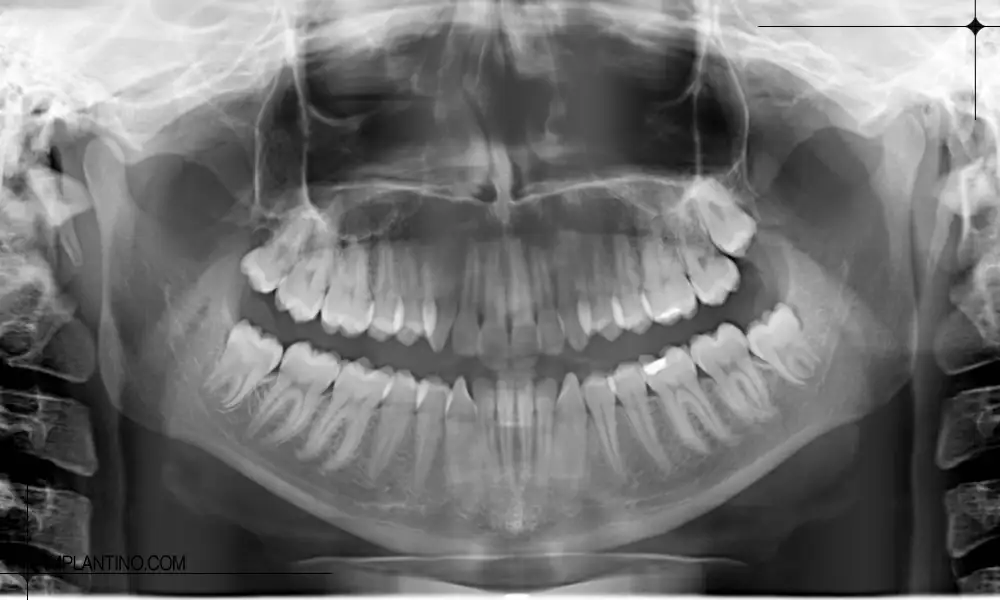

عکس opg چیست؟

OPG که مخفف Orthopantomogram است، یک نوع رادیوگرافی پانورامیک محسوب می شود که تصویری دو بعدی از کل فک بالا و پایین، دندان ها و بافت های اطراف آن ارائه می دهد. برخلاف رادیوگرافی تک دندان، OPG دید کلی و یکپارچه ای از دهان فراهم می کند و برای تشخیص مشکلات گسترده تر، برنامه ریزی درمان های پیچیده و پایش وضعیت دندان ها و فک بسیار کاربرد دارد.